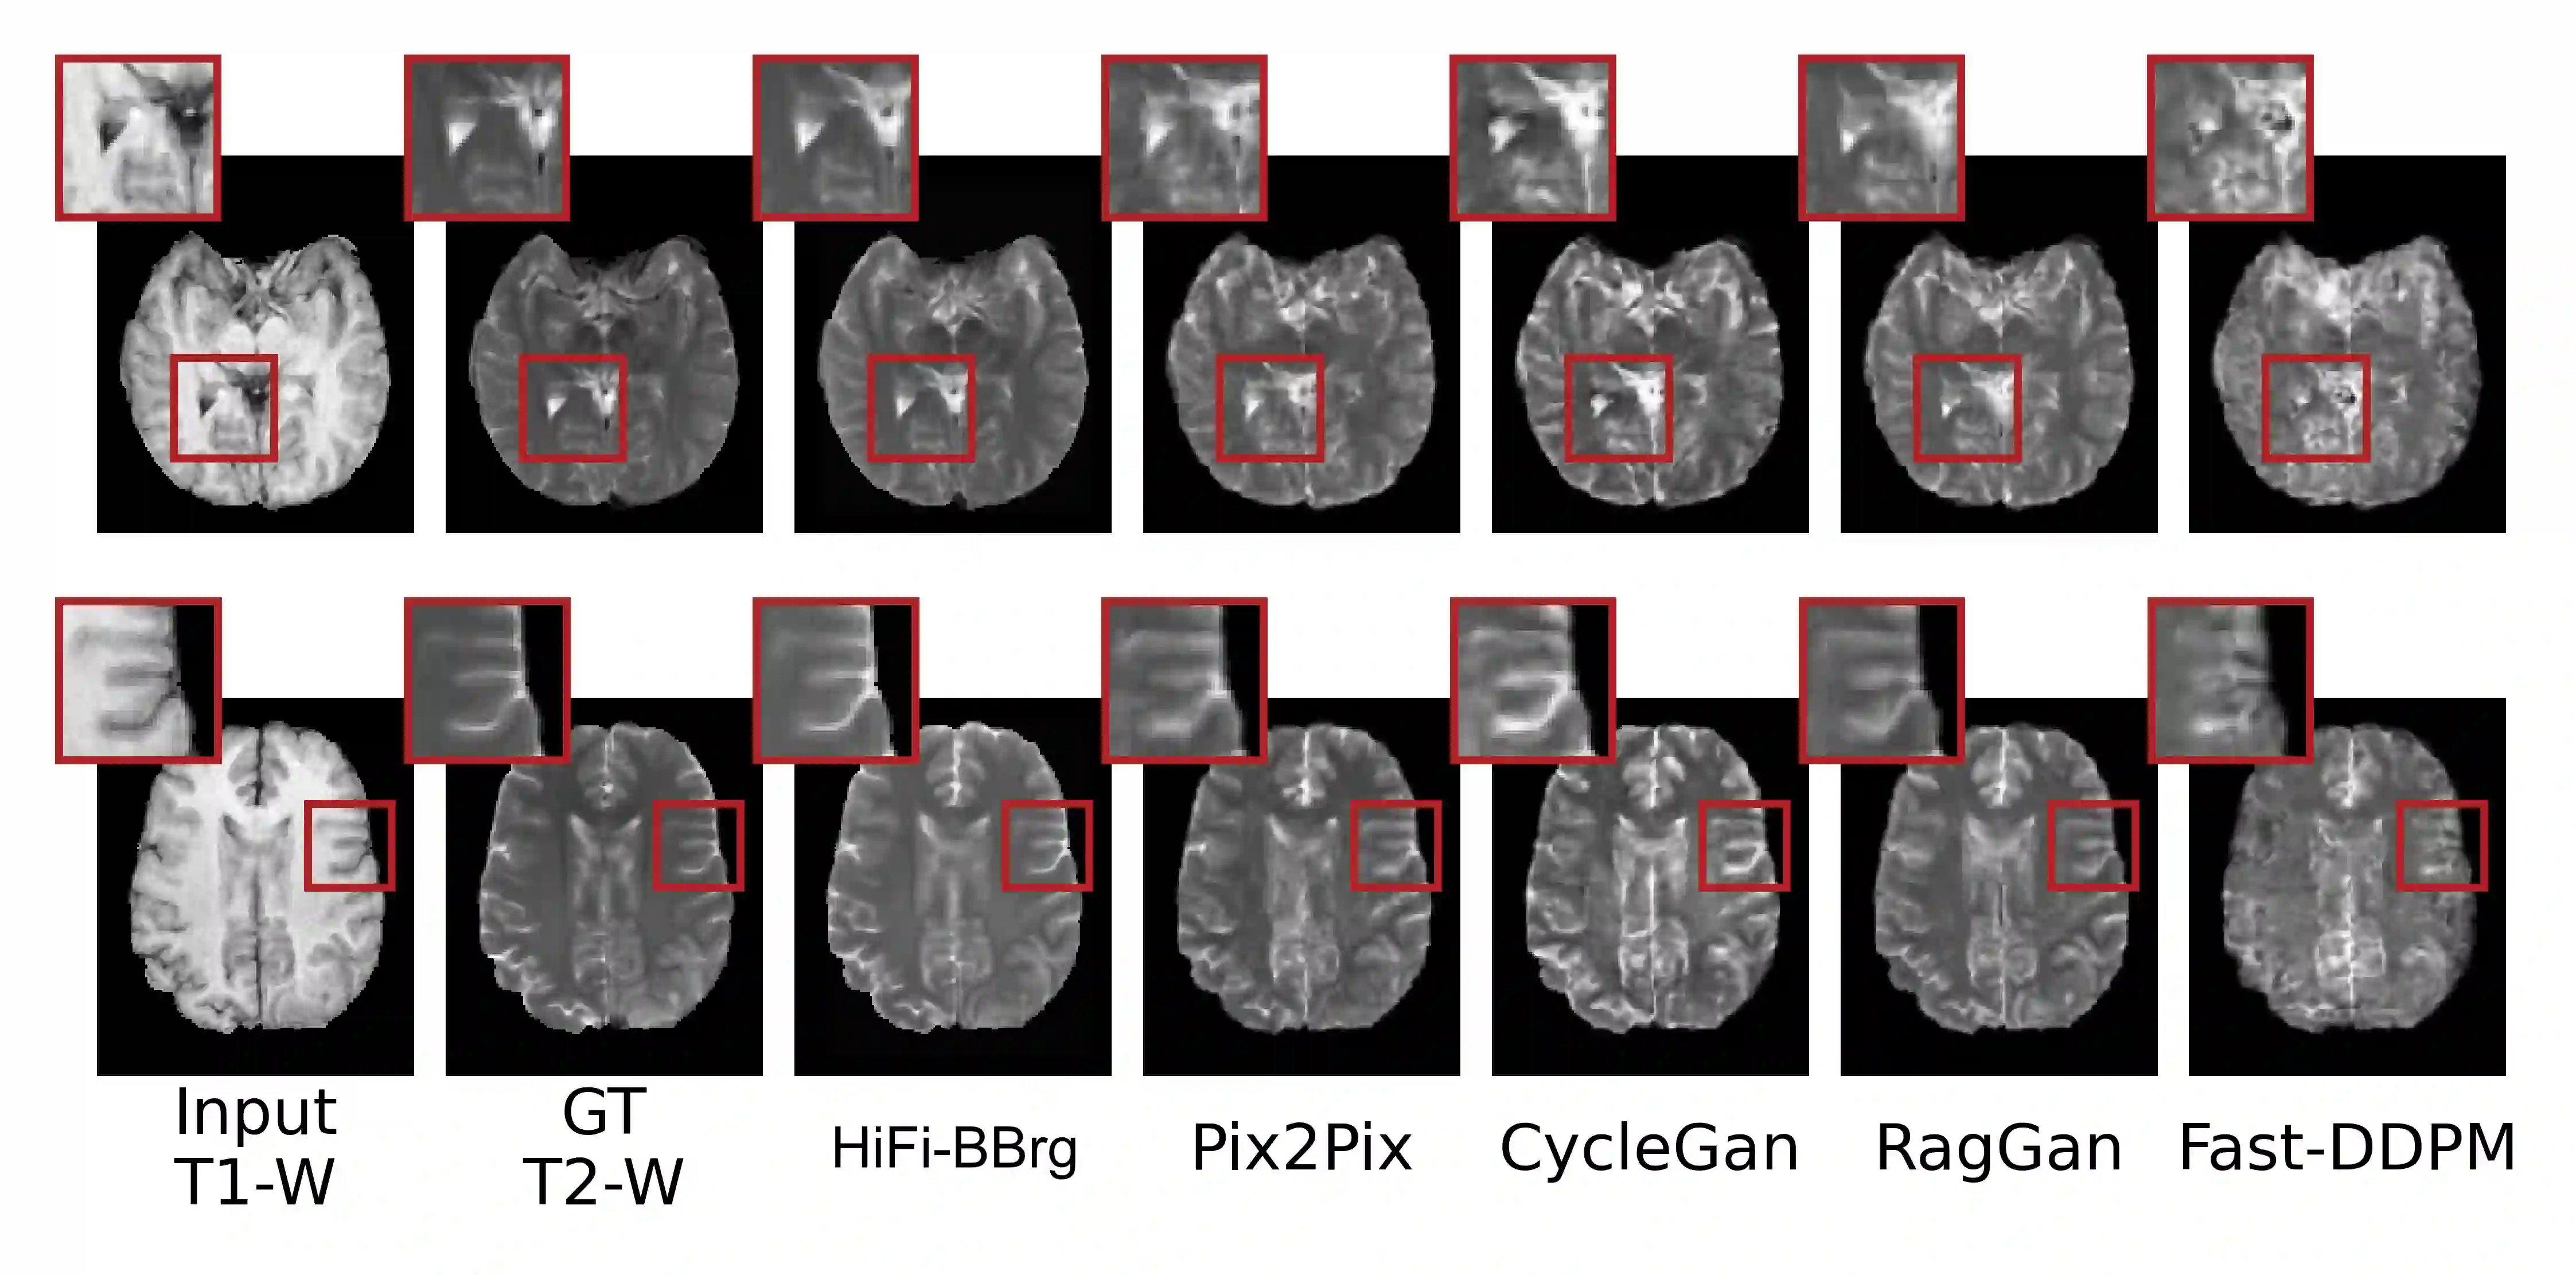

Recent studies have shown that diffusion models produce superior synthetic images when compared to Generative Adversarial Networks (GANs). However, their outputs are often non-deterministic and lack high fidelity to the ground truth due to the inherent randomness. In this paper, we propose a novel High-fidelity Brownian bridge model (HiFi-BBrg) for deterministic medical image translations. Our model comprises two distinct yet mutually beneficial mappings: a generation mapping and a reconstruction mapping. The Brownian bridge training process is guided by the fidelity loss and adversarial training in the reconstruction mapping. This ensures that translated images can be accurately reversed to their original forms, thereby achieving consistent translations with high fidelity to the ground truth. Our extensive experiments on multiple datasets show HiFi-BBrg outperforms state-of-the-art methods in multi-modal image translation and multi-image super-resolution.

翻译:近期研究表明,与生成对抗网络(GANs)相比,扩散模型能生成更优的合成图像。然而,由于固有的随机性,其输出常具有非确定性且缺乏对真实数据的高保真度。本文提出一种用于确定性医学图像翻译的新型高保真布朗桥模型(HiFi-BBrg)。该模型包含两个相互独立又彼此促进的映射:生成映射与重构映射。布朗桥训练过程通过重构映射中的保真度损失与对抗训练进行引导,确保翻译后的图像能精确还原至原始形态,从而实现与真实数据高度一致的确定性翻译。我们在多个数据集上的大量实验表明,HiFi-BBrg在多模态图像翻译与多图像超分辨率任务中均优于现有最优方法。